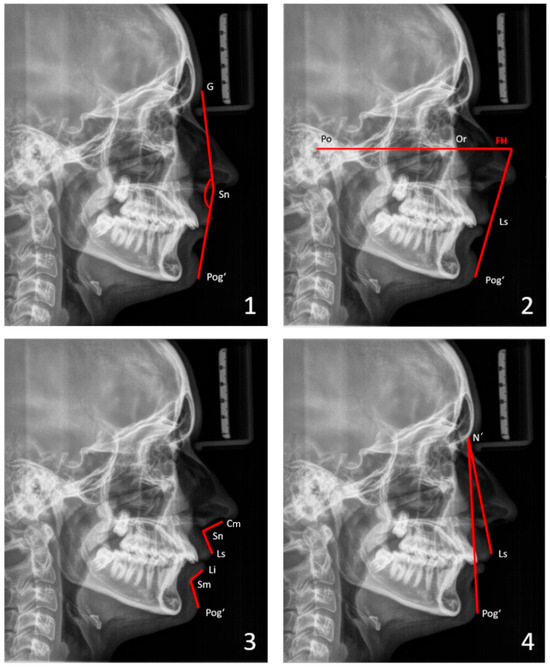

Background: The aims of the study were to describe facial morphology and analyze facial growth in adolescents with Robin sequence (RS) or Stickler syndrome. Methods: The facial morphology, mandibular size, and facial growth of 69 adolescents (ages 12–18) with RS were analyzed using existing cephalometric radiographs (n = 37) and photographs (n = 69). All participants were followed in our institution since birth. None underwent growth-modifying treatment for micrognathia during infancy, but all had conservative orthodontic treatment during adolescence. Results: Cross-sectional cephalometric analysis according to Tweed revealed differences in RS adolescents as compared with reference values, such as a proportionate retrusion of both jaws, as indicated by decreased SNA and SNB angles (p < 0.05). This finding was mostly associated with skeletal Class I (62.2%) and a vertical facial pattern as indicated by increased FMA and CoGoMe angles (p < 0.05). In Delaire’s analysis, patients showed decreased maxillary, maxillary alveolar (p < 0.05), and mandibular body territories (p > 0.05) but increased ramus (p > 0.05) and nasopremaxillary territories (p < 0.05). According to Ricketts’ analysis, mandibular width was decreased in half of our patients (p > 0.05). The mandibles were harmoniously downsized before and after the growth spurt (p < 0.05); however, they exhibited greater growth velocities than controls. A long-term study during puberty revealed an increase in SNB angles and a decrease in ANB angles (both p < 0.05), which improved the maxillomandibular relationship. Additionally, the vertical facial pattern attenuated (FMA, SNGoGn, and CoGoMe angles decreased; p > 0.05). On cross-sectional photographic analysis, 33.3% of patients had an orthofrontal (straight), 59.4% a cisfrontal (convex), and 7.3% a transfrontal (concave) profile. Their vertical facial proportions were normal. In the subjective profile analysis, most patients (approximately 84%) had good or acceptable profiles, with no major deficit of chin projection. The initial degree of neonatal retrognathia and type of cleft palate surgery did not affect major skeletal parameters (p > 0.05). However, the degree of neonatal functional impairment affected the vertical parameters (SNGoGn, FMA angle; p < 0.05). Conclusions: Overall, RS patients presented a bi-retrognathic profile, a normal jaw relationship, and a tendency toward a vertical growth pattern. Partial mandibular catch-up growth occurred during the pubertal growth spurt. The degree of neonatal retrognathia does not predict further mandibular growth. Full article